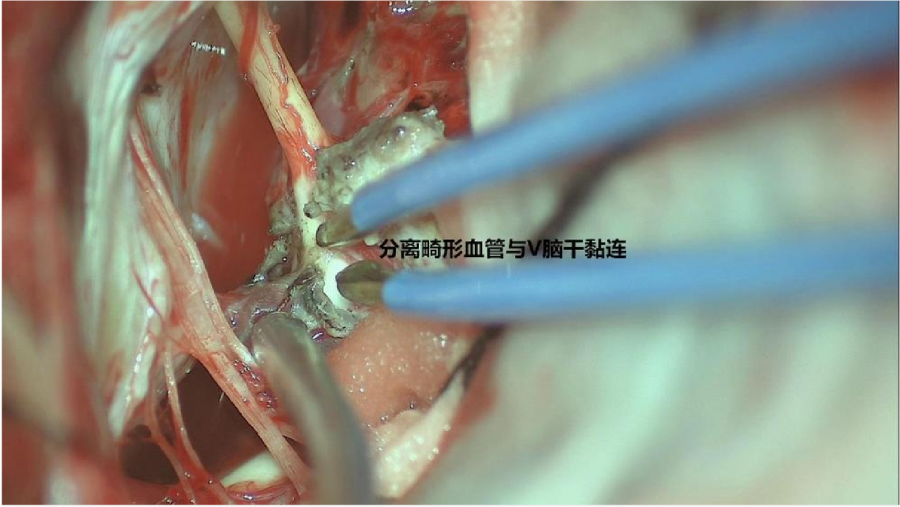

⾏左侧远外侧⼊路脑⼲⾎管畸形切除术,术中所⻅:

3、脑⼲动静脉畸形⼿术切除是注意辨别供⾎动脉与引流静脉,其往往不似其他部位的动静 脉畸形,有叫粗⼤的引流静脉。术中如果不能辨清各⾎管来源与去处,往往会造成不可估量的损失。